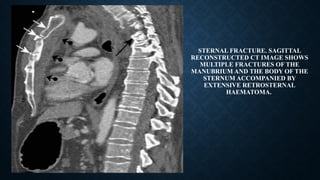

STERNAL FRACTURE. SAGITTAL

RECONSTRUCTED CT IMAGE SHOWS

MULTIPLE FRACTURES OF THE

MANUBRIUM AND THE BODY OF THE

STERNUM ACCOMPANIED BY

EXTENSIVE RETROSTERNAL

HAEMATOMA.

STERNUM FRACTURE

• Sternal fractures: 3–8% in blunt chest trauma.

• Main mechanism: deceleration injury/direct blow to the anterior chest wall.

• Difficult to detect on lateral chest radiographs .

• Almost always accompanied by anterior mediastinal haemorrhage, which has a preserved fat

plane with the aorta, as opposed to an anterior mediastinal haemorrhage secondary to aortic

injury, which will present with a lost fat plane with the aorta.